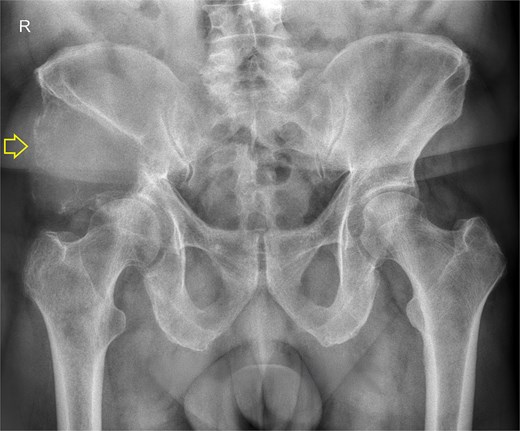

The pelvic radiograph showed a lytic lesion measuring 8 × 8 cm on the outer edge of the right iliac bone (Fig. 1), which was initially considered as a giant cell tumor. Given these findings, a computed tomography (CT) scan of the thorax, abdomen, and pelvis was requested to evaluate possible tumor dissemination. The CT scan revealed a heterogeneous expansive mass measuring 113 × 96 × 100 mm with destruction and remodelation of the right iliac bone (Fig. 2), a 45 × 38 mm mass in the right chest wall with heterogeneous contrast (Fig. 3), three pulmonary nodules in the left lower lobe (5–12 mm) (Fig. 4A) and multiple hypo- and isodense hepatic lesions (10–28 mm in both hepatic lobes) (Fig. 4B). That same month, two biopsies were performed. The first, from the right chest lesion, showed positivity for CD34, BCL-2, and STAT6 in the immunohistochemical study, confirming the presence of an SFT. The second, from the right iliac crest lesion, showed a spindle-cell sarcoma with bone invasion, with immunohistochemistry positive for CD34 and vimentin, a Ki-67 index of 10%, and negative for cytokeratins. This biopsy was processed in a public hospital pathology laboratory, where reagents for BCL-2 and STAT6 were not available at the time of analysis. Based on the histologic appearance, partial immunophenotype, and clinical context, the iliac lesion was considered highly suggestive of metastasis from the chest wall tumor. However, due to the patient’s rapid clinical deterioration and subsequent death, confirmatory testing by STAT6 immunostaining could not be performed.

Pelvis radiograph, anterior view. A well-defined lytic lesion measuring 8 × 8 cm is identified in the right iliac wing.